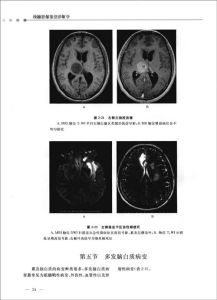

1.CT嚴重外傷型急性硬膜下血腫CT表現為大腦凸面的新月形高密度區,大部分血腫密度較均勻;可伴有其下方的腦實質不均勻密度的挫裂傷,呈弧形或不規則形,並有不等比例的腦內結構的占位效應。病變常見於大腦凸面,但也可發生於額下、顳下或大腦半球間的區域,額下和顳下病變,有時軸位掃描常難以發現,可行冠狀位掃描,或調整腦組織窗觀察病灶。在一些貧血患者,當其血色素低於8~10g/dl時,急性硬膜下血腫可呈等密度。鑑別等密度血腫較為困難,可仔細觀察腦白質是否壓迫移位或套用高解析度的掃描技術。

慢性硬膜下血腫的CT特徵大腦邊緣的新月形或梭形病變,通常為均勻的中低密度,或相對等密度影,常可看到血塊一液體分層樣改變,偶爾可見鈣化影。慢性型可見同一患者的多發病灶,伴有不同慢性期、不同形狀和不同密度表現(圖19-6)。慢性型等密度血腫更難於發現,在CT上僅見占位效應,可有以下徵象用於鑑別:①腦溝消失;②患側灰白質界面內移;③增強後強化的囊樣改變;④皮質靜脈的移位。